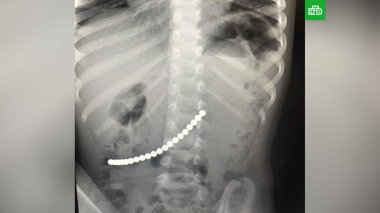

Մերձմոսկվայում բժիշկները փրկել են 20 մագնիս կուլ տված երեխային

Մերձմոսկովյան Բալաշիխայի շրջանային հիվանդանոց որովայնի ցավերով երկու տարեկան երեխա է ընդունվել: Ախտորոշման ընթացքում տղայի աղիներում օտար մարմիններ էին...